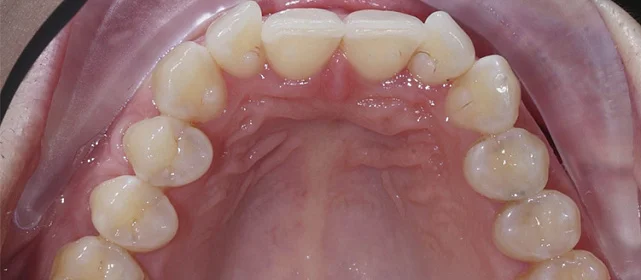

Диагностика

Верхняя челюсть выступала вперёд относительно нижней с обеих сторон (II класс по Энглю). Обе челюсти сужены, зубы стояли скученно. Нарушена кривая смыкания — жевательные зубы были на разной высоте. На двух передних зубах верхней челюсти ранее установлены металлокерамические коронки.

Прозрачные элайнеры Click на обе челюсти. Расширить зубные дуги, убрать скученность, исправить прикус и выровнять линию смыкания. Лечение с учётом имеющихся коронок. Основной набор — 31 капа. Срок — около 1,5 лет.

Проблема: Пациентку беспокоили неровные зубы и неправильный прикус. При осмотре нашли сразу несколько проблем: обе челюсти сужены, зубы стоят скученно, верхняя челюсть выступает вперёд (II класс по Энглю), кривая смыкания деформирована — жевательные зубы на разной высоте. На двух передних зубах верхней челюсти стояли старые металлокерамические коронки, которые нужно было учитывать при планировании.

Решение: Поставили элайнеры Click на обе челюсти. Основной набор — 31 капа, плюс два дозаказа: 26 и 7 кап, итого 64. При этом лечение уложилось в 20 месяцев — быстро для такого объёма работы. Расширили дуги, убрали скученность, исправили прикус, выровняли линию смыкания. Ретейнер поставили только на нижнюю челюсть. На верхней от ретейнера отказались сознательно — на передних зубах коронки, и проволока там не ляжет корректно. Вместо этого изготовили ретенционные капы на обе челюсти. Ортопедию — замену старых коронок — пациентка будет проходить у себя в городе.

Непростой случай: II класс, сужение, скученность, деформация кривой Шпее и металлокерамические коронки на 11 и 21. Коронки ограничивают варианты ретенции — на верхней челюсти вместо ретейнера используем капы. Это осознанное решение, принятое совместно с пациенткой. 64 капы за 20 месяцев — хороший темп для такого объёма. Основной набор сделал базу, дозаказы довели до нормы.